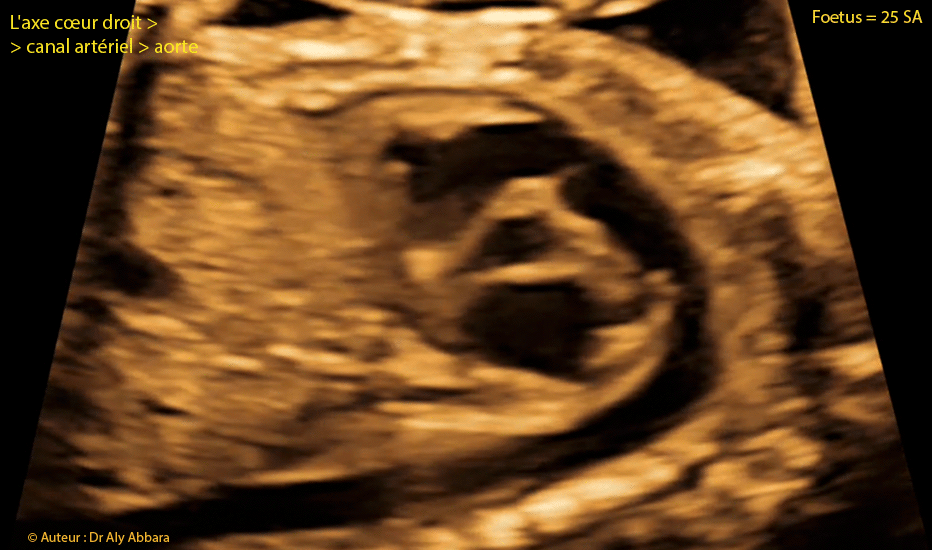

Coeur foetal - 25 SA - Axe coeur droit - tronc pulmonaire - canal artériel - aorte

Image échographique animée montrant les éléments anatomiques composant l'axe cœur droit - canal artériel - aorte :

- Le ventricule droit (VD) ; la voie d'éjection du ventricule droit ; la valve pulmonaire (VP) et ensuite le tronc pulmonaire (TP) qui se divise sur cette coupe en deux branches : l'artère pulmonaire gauche (APG) et le canal artériel qui permet au tronc pulmonaire de se connecter à la crosse de l'aorte à proximité de l'aorte descendante.

Sur cette coupe on identifie également : l'oreillette gauche (OG) ; la valve mitrale (VM) ; partiellement le ventricule gauche (VG) et enfin, le septum interventriculaire (SIV).

Cette coupe est utilisée pour mesurer le Doppler du canal artériel.

Fœtus âgé de 25 SA.